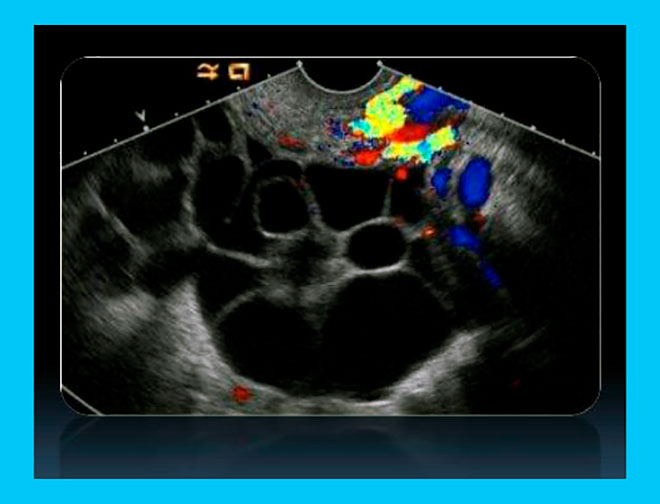

- Средняя. Боль средней интенсивности, возникает тошнота или рвота, на УЗИ обнаруживается скопление жидкости в брюшине, яичники увеличиваются до 12 см.

- Тяжелая. Сильное увеличение живота в результате развития асцита, задержка мочеиспускания, яичники более 12 см. По статистике такая степень СГЯ развивается в 0,3-8% случаев.

- проведение УЗИ и фолликулометрии при стимуляции суперовуляции;

Диагноз гиперстимуляция яичников ставится на основании показателей артериального давления, измерения суточного диуреза, объемов окружности живота. В обязательном порядке проводится лабораторное исследование – общий и биохимический анализ крови, гемостазиограмма. На этапе диагностики патологии также проводится УЗИ малого таза, брюшины и плевральных полостей.